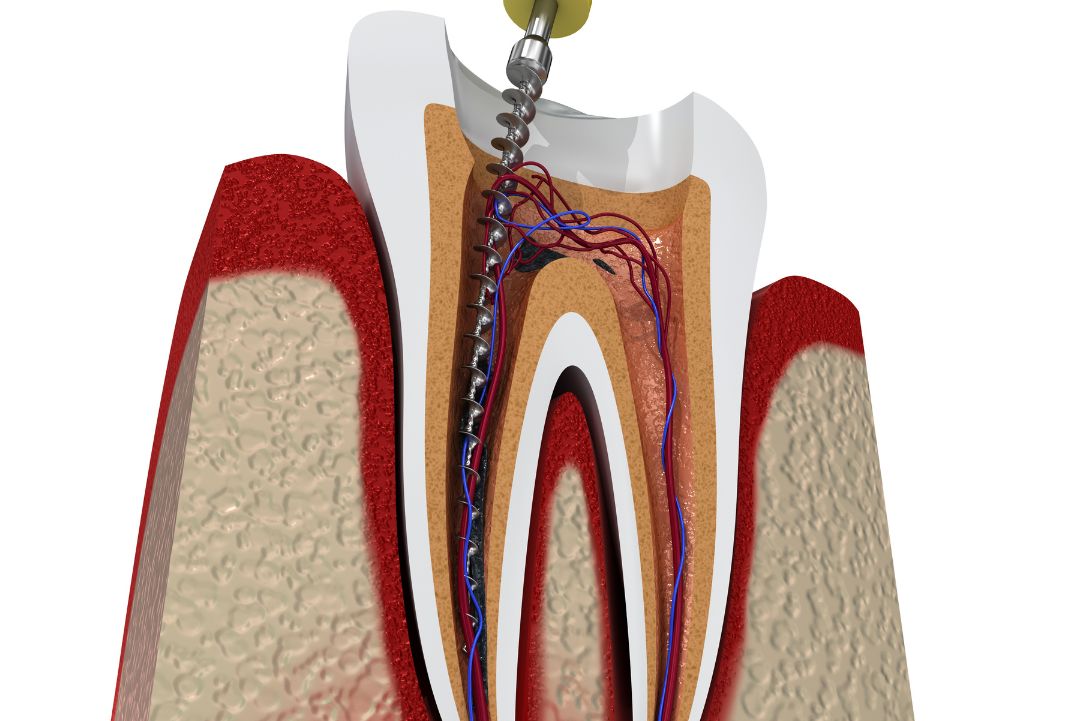

Traitement de canal